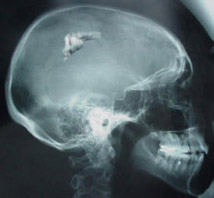

Sam Sherman is convinced aliens put a device into his skull

The next day Sherman got an intense headache that was to last for the next several days. He had suffered from migraines in his youth and was worried that this signified that they were coming back. Concerned, he went to neurologist Bently Suffolk in Pensacola. Dr. Suffolk found a small scar of recent origin on the back of the patient's head. Sherman could not remember getting injured there recently so as a precaution Dr. Suffolk ordered an x-ray of Mr. Sherman's head. The x-ray showed that a foreign object was imbedded in a section of the brain.

"The object is located in the parietal lobe of Mr. Sherman's brain." states Dr. Suffolk. "It is approx. 5 cm long and 1 cm wide. A CT scan further revealed that the object is made of metal and is embedded in the post central gyrus. No brain functions seem to be disturbed but since the gyrus is responsible for feeling sensations it's possible that the object is causing a feedback loop into the lobe which is causing Mr. Sherman's headaches."

"Modern medical science could implant an object of that size into the brain but it would require removing a sizable section of the skull. The scar on the exterior of the skin was only approx. 1 1/2 cm wide. This would seem to imply that the object entered Mr. Sherman's head with some force but there was no damage to the brain that would be associated with such a trauma. Medication seems to be controlling the worst aspects of Mr. Sherman's headaches and because of the major surgery involved in removing the object I have recommended against it."